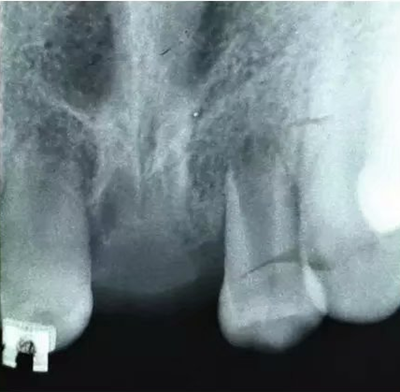

車禍后,一名10歲男孩被送往Shariati醫(yī)院急診科。診斷出上頜中切牙的脫落和側(cè)切牙的嵌入(圖1)。脫落的中切牙丟失了,沒有進行再植。全景片示除第二磨牙外的恒牙列(圖2)。

圖1. 初診口內(nèi)照

圖2. 初診全景片